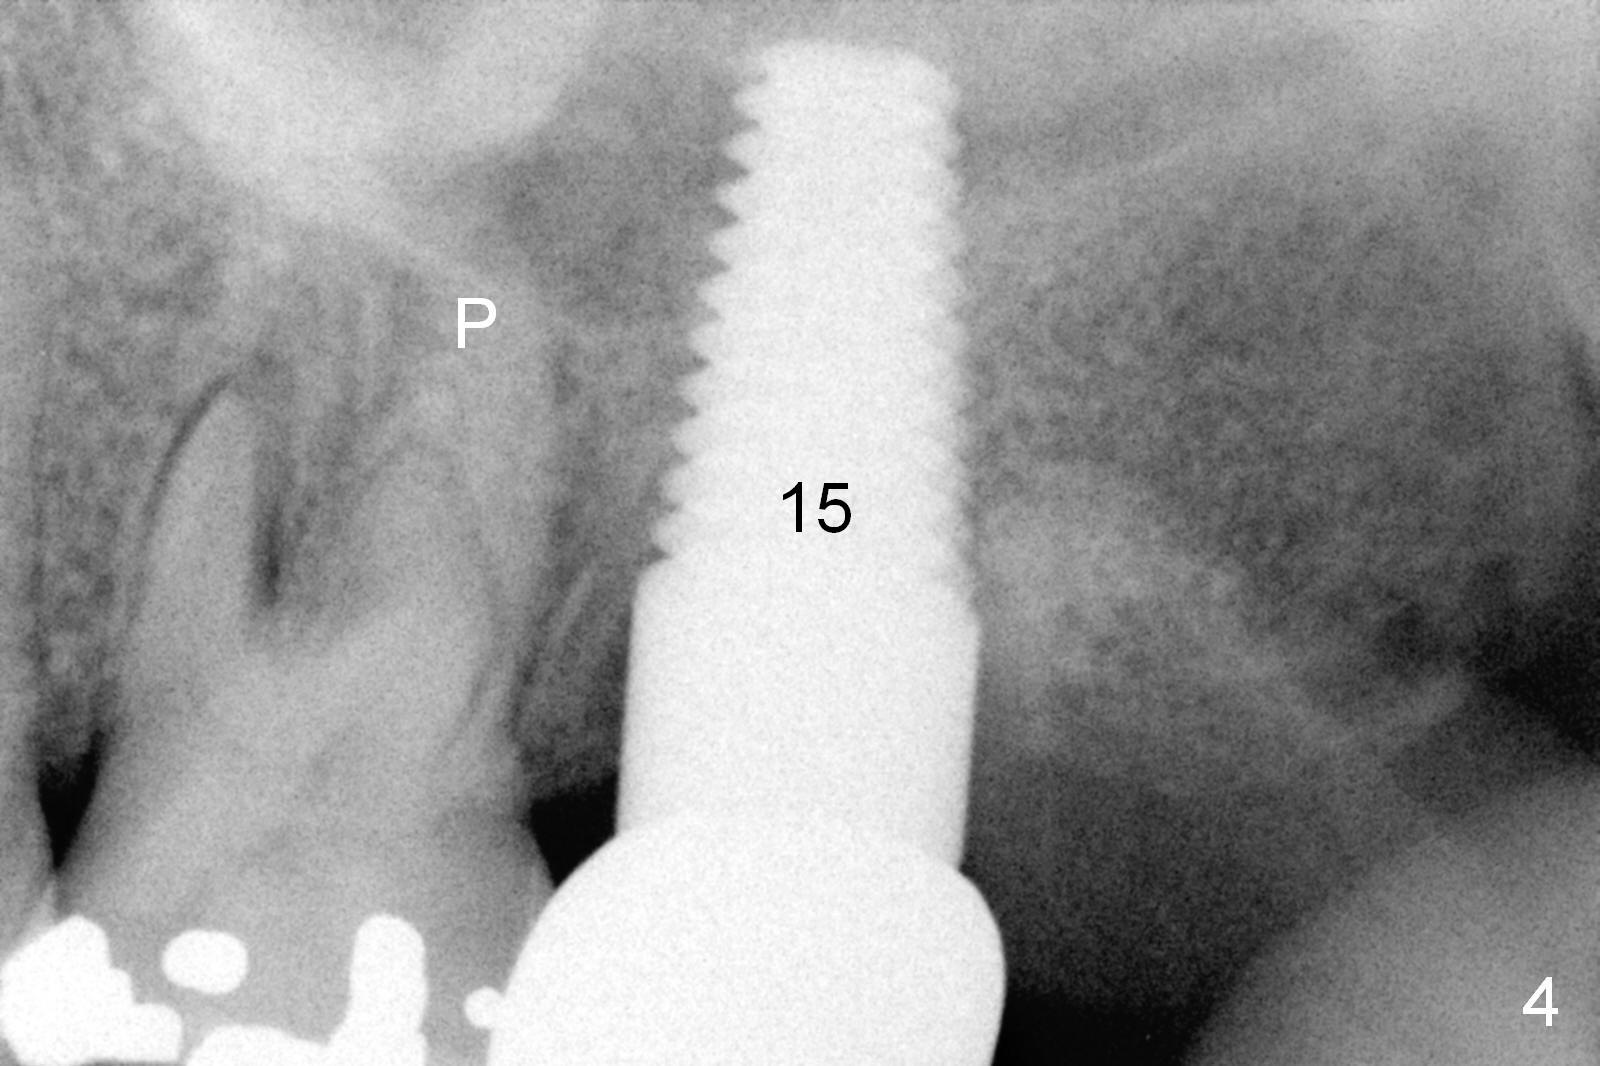

A 48-year-old lady has 4 relative contraindications to immediate implant: 1. infection is so severe at the site of #14 (the posterior maxilla with low bone density, Fig.4,5) that there is no enough bone to support the implant (Fig.7 illustration (1, 2); 2. dental insurance runs out; 3. she shows late in the afternoon when there is not enough staff; 4. she has had 2 immediate implants placed (Fig.4: #15 (3,4)). After socket preservation (Fig.8,9), she is most likely to return for implant placement.

It is noteworthy that the tooth #14 was less affected than #15 22 months earlier (Fig.1 (CBCT sagittal section), 2 (axial), 3 (coronal)). Calculus on the surface of the palatal root (Fig.6 P) is associated with the palatal abscess (Fig.5 P). S: septum.